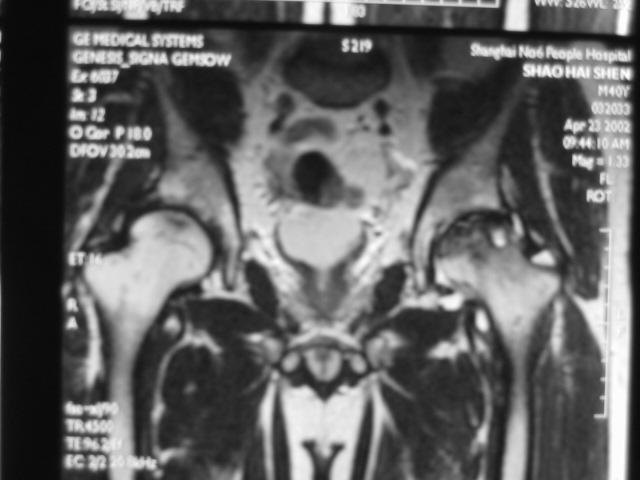

Ⅳ期

关节软骨彻底破坏,髋关节间隙狭窄,合并关节退行性改变。

髋臼面软骨下骨质可出现囊性变,髋臼缘骨赘增生。

股骨头因骨坏死、囊变、骨折而显著塌陷、变形,受累范围可局限于股骨头上部或累及整个股骨头。

股骨头出现分节碎裂、骨折移位。